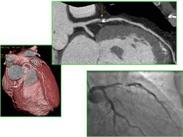

變異型心絞痛

• 變異型心絞痛

628健康網為您分享有關變異型心絞痛的癥狀,變異型心絞痛的治療方法,變異型心絞痛的預防知識,變異型心絞痛的癥狀圖片,變...